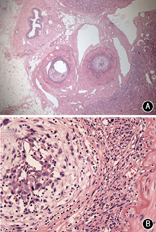

患者女,35岁,因发作性腰背疼痛1年,加重2个月余,于2014年12月入住北京协和医院。患者于2013年12月中旬无明显诱因出现头痛、心慌、大汗,无恶心、呕吐,未重视。2014年1月,患者因头痛伴血压明显升高至200/110 mmHg(1 mmHg=0.133 kPa)就诊于外院,左肾肾小球滤过率(GFR) 7.48 ml/min,超声提示左肾明显萎缩,大动脉造影显示左肾动脉起始段假性动脉瘤形成,压迫左肾动脉导致远端不显影;遂行左侧无功能肾切除术。术后病理提示左侧肾盂组织慢性炎,左肾组织间质少许慢性炎细胞浸润并玻璃样变性,左输尿管残端黏膜组织慢性炎。2014年4月,患者突发少尿,血肌酐(Cr) 795 μmol/L,考虑急性肾功能衰竭,开始行肾脏替代治疗,腹部增强CT提示L1水平腹主动脉左侧动脉瘤,大小约1.9 cm×1.7 cm,右肾动脉闭塞,右肾实质未见异常,腹膜后肿大淋巴结,腹主动脉周围可见软组织密度影包绕,增强扫描未见明显强化(图1A)。肾动脉造影提示右肾动脉主干仅线形显影,余完全闭塞。2014年5月尝试行右肾自体肾移植术,但术中发现肾动脉及其分支全部堵塞,遂切除右肾。术后病理显示右肾脏动脉间叶组织肿瘤,结合免疫组化染色符合血管内膜肉瘤,可见右肾脏肾小球及肾小管透明变性、凝固性坏死伴灶状炎细胞浸润及间质纤维结缔组织增生,右输尿管残端及右肾周脂肪组织未见肿瘤组织(图2);免疫组化:波形蛋白(Vimentin)(+),肌动蛋白(actin)(+),增殖指数(Ki-67)(+,约10%),簇分化抗原(CD)31、CD163、CD68、CD3、白细胞共同抗原(LCA)、B细胞淋巴瘤白血病基因-2(BcL-2)、CD34、高分子量钙调结合蛋白(h-Caldesmon)、平滑肌肌动蛋白(SM-actin)、CD21、CD35、D2-40、CD123、CD20、S-100、第Ⅷ因子相关抗原(FⅧ-RAg)、结蛋白(Desmin)、间变性淋巴瘤激酶(ALK)、CD99、角蛋白(CK)、上皮膜抗原(EMA)、CK18、黑色素瘤相关抗原(HMB45)均(-);未进行后续辅助治疗。2014年7月,患者复查胸腹部CT血管造影(CTA),提示腹膜后肿物包绕T12、L1椎体水平腹主动脉、腹腔干及双肾动脉残端,左肾动脉残端瘤样扩张,大小约2.3 cm×2.1 cm×2.3 cm;患者未治疗。2014年12月3日,患者因腰部剧烈疼痛复查肾动脉超声提示腹主动脉瘤可能性大,大小约5.7 cm×4.0 cm,左肾动脉主干受压前移。当日夜间,患者血压最高达190/110 mmHg,次日早晨患者因失血性休克急诊行大动脉造影提示左肾动脉残端假性动脉瘤(图1B),考虑左肾残端动脉瘤破裂出血,遂行腹主动脉假性动脉瘤腔内隔绝术,术中对支架行肠系膜上动脉开窗。2015年1月,患者上厕所时突发右侧腰背部持续钝痛;腹主动脉CTA考虑腹主动脉假性动脉瘤形成。主动脉造影提示原主动脉支架上方造影剂轮廓不规则,考虑主动脉假性动脉瘤形成(图1C),遂再次行腔内隔绝术,支架放置于腹腔干上方。术后行PET/CT提示腹主动脉(T10~L2水平)周围巨大肿块,包裹腹腔干及肠系膜上动脉,范围约11.8 cm×9.0 cm×10.0 cm,考虑恶性病变,全身其余部位未见明确转移(图3)。出院后患者未行辅助治疗。2015年3月,患者因心力衰竭去世。